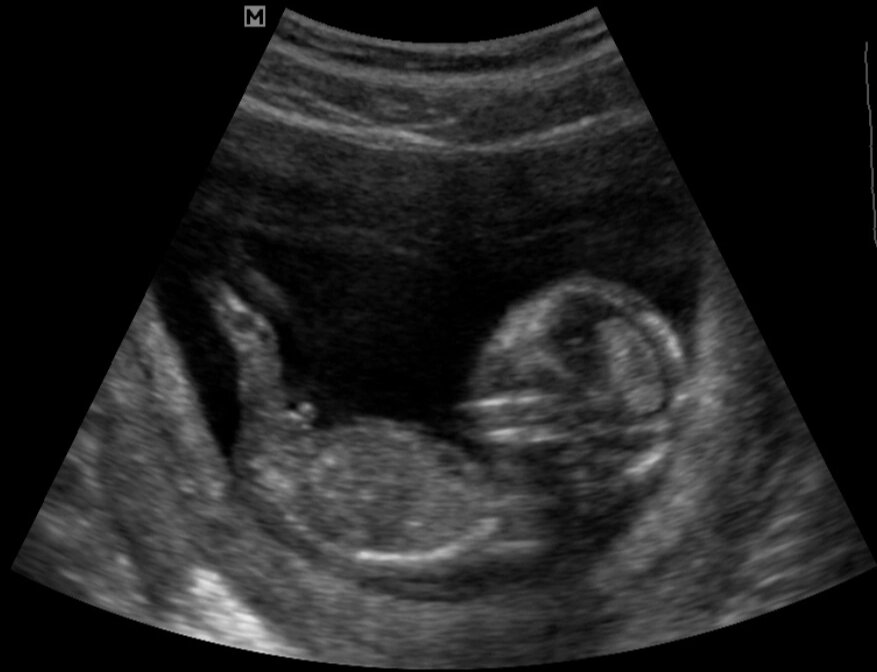

Недовольно упирается ножками

Врач смеялась и ругала меня, говорила что нужно прекратить реветь, а то она измерить не может нужные параметры. А я там рыдала взахлёб от приступа любви и нежности к этому маленькому чуду, которому очень не нравилось УЗИ и он упёрся ножками в живот. Тогда я этого не чувствовала. Зато запомнилось его недовольство, которое он проявлял на каждом УЗИ.

Удивительно, но мне в этот же день назвали пол и не ошиблись. Несколько остальных УЗИ его только подтвердили. С ребёнком было все отлично, по размерам даже опережал на две недели.